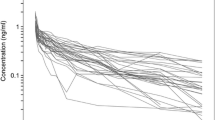

This analysis was based on the concentration–time profiles of dexmedetomidine collected from 27 patients (Fig. 1). Table 1 lists the patients’ demographic and the available covariates. The available data consisted of 368 dexmedetomidine concentration measurements (Fig. 1).

The model-building process started with a two-compartment model and proportional residual error model based on literature findings. This model turned out to be the best to describe the data. The simpler one-compartmental model and more complex three-compartment model were not superior based on the applied criteria. Similarly the additive or combined additive and proportional error models did not lead to model improvements based on AIC criterion. Supplemental Fig. 1S shows typical goodness-of-fit plots for the final model. The individual predictions are close to that of the experimental data with no major systematic bias, indicating good performance of the model, which is also confirmed by other goodness-of-fit plots. The VPC for the dexmedetomidine concentration were used to assess the simulation properties of the model. Figure 2 shows the results. VPC plots indicate that both the central tendency of the data and the variability at a particular sampling time were recaptured well. There are no major misspecifications in that graph.